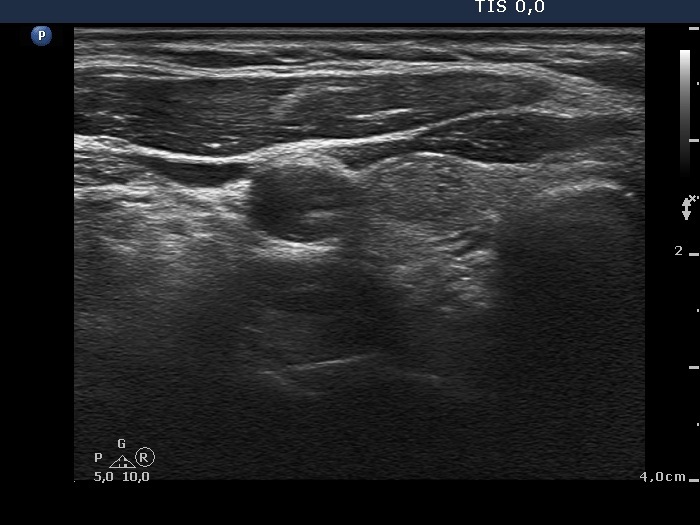

Ultrasonography. The thyroid was echonormal. There was a minimally-moderately hypoechogenic nodule in the right while a cystic nodule in the left lobe. There were numerous hyperechogenic figures both in the cystic and in the lower solid part of the lesion. The lesion presented no vascularization.

Comment. The presentation of the bright hyperechogenic granules are relatively unusual, they were mostly located within the solid part causing a false impression of starry sky phenomenon. In fact, they were comet-tail artifacts.